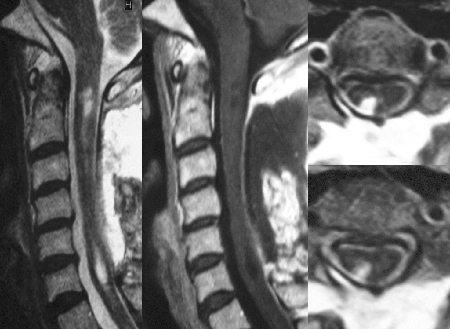

箸が使えないなどの右手の運動障害があり,歩行障害により杖を必要とした患者さんです.MRIでは脊髄全体が白くなり,脊髄が全体に腫れています(左図左).造影MRIで腫瘍が卵円形に白く描出されます(左図中央).血管撮影では腫瘍が卵円形に造影されます(左図右).手術では,脊髄表面にオレンジ色の腫瘍を認めました(下図矢印).

腫瘍摘出後,右手の運動障害は改善して箸が使えるようになり,歩行時に杖を必要としなくなりました.術後のMRIでは,脊髄が白くなくなり脊髄の腫れが減少していることが分かります(下図左).造影剤を使ったMRIでは卵円形に白く描出された腫瘍が完全に消失しています(下図中央).腫瘍を摘出したところは脊髄の背面右側に認められます(下図右).

摘出前

摘出後